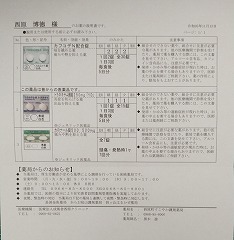

2024.3.9 鼻炎と目のかゆみがひどく、オロパタジン⇒デザレックス&点眼薬 アレジオン に変更 2.10 血液検査結果

レボセチリジン塩酸塩錠5mg「武田テバ」 モンテルカスト錠10mg「トーワ」